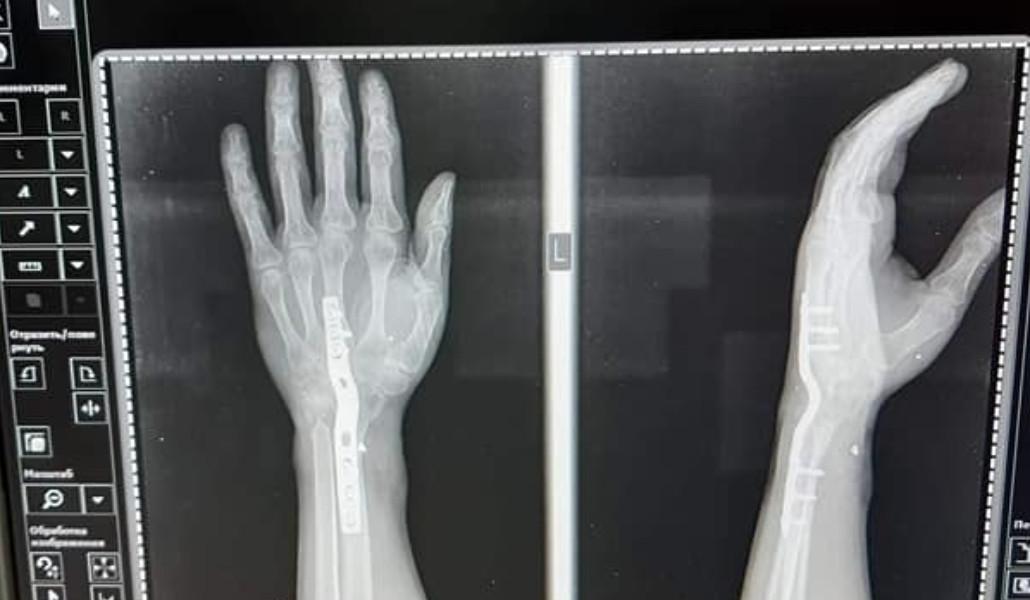

«Ես շատ ուրախ կլինեի, որ իրապես հաշմանդամ չլինեի և թքած ունեմ դրանց տված 60.000 դրամի վրա, բայց իրականում իմ Ձեռքերը կոտրված են և ես իմ ռենտգենի լուսանկարները Ձեզ եմ ներկայացնում, երկու ձեռքս էլ ջարդված է, երկաթ է դրված և դա պարզ երևում է ռենտգենով։